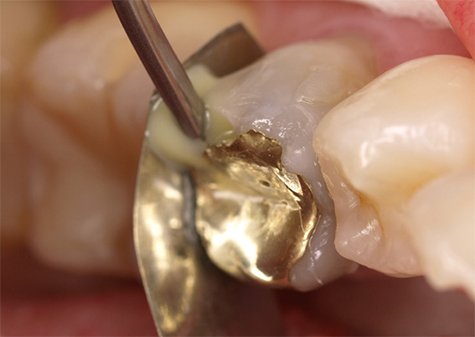

Bovendien biedt Futurabond U het beslissende voordeel dat het een betrouwbare hechting zonder extra primer ook aan diverse materialen als metaal, zirkoon-, aluminiumoxide en silicaatkeramiek waarborgt. Daarom is het op een bijzondere manier ook geschikt voor intra-orale reparaties. De foto’s 7-9 laten een typische klinische casus zien, waarbij het behoud van de aanwezige gouden restauratie gepaard ging met de reparatie van harde tandsubstantie. Hier is het goede hechtende vermogen van het adhesief aan compleet verschillende materialen de voorwaarde voor een succesvolle en duurzame restauratie.

Afb. 7: Applicatie van Futurabond U op gouden restauratie en harde tandsubstantie

Afb. 8: Applicatie van een vloeibaar composiet

Afb. 9: Toestand na succesvolle reparatie